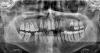

ОПТГ от 2 сентября. Слегка нечеткая.

11, 21: сломаны 12 лет назад. в 2007 депульпированы, вставлены стекловолоконные штифты.

13, 12, 22, 23: до 2007 были съедены кариесом, в 2007 депульпированы, каналы запломбированы гуттаперчевыми штифтами методом латеральной конденсации. Не шатаются, не беспокоят никого кроме ортопедов.

27, 28: средний кариес. Хотя на каком-то из них начинают появляться признаки пульпита (самопроизвольная боль). Планирую санировать на следующей неделе.

26: в детстве был запломбирован резорцин-формалиновым методом, в 2007 был вскрыт, подготовлен под вкладку, не перенес всего этого, раскололся, сгнил и на данный момент (18.09.09) удален. Такой вот ужас.

18, 48: глубокий кариес. Удалены 19.09.09 по моему желанию.